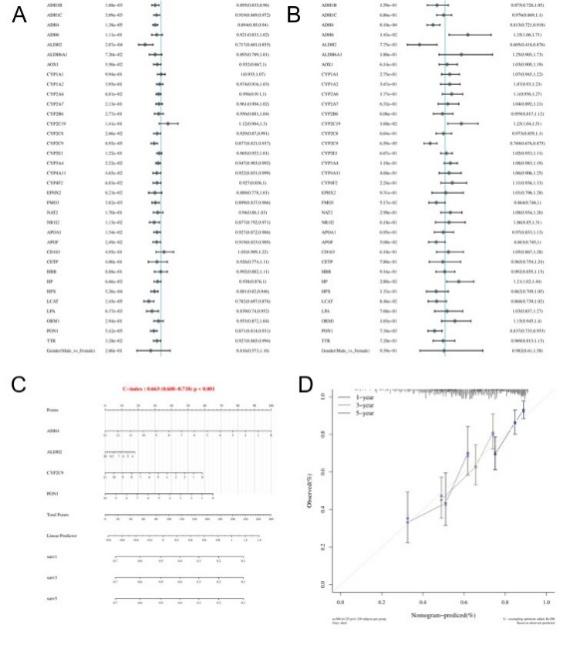

We performed survival analysis on the DEGs, indicated that the majority of these genes were associated with poor prognosis. Specifically, EZH2, GINS1, and MCM2 (Figure 6) were found to be adverse prognostic markers even after adjusting for covariates, while ALDH2, ADH4, CYP2C9, APOF, and PON1 were identified as favorable prognostic factors after covariate adjustment (Figure 7). Using both univariate and multivariate analyses, we identified variables suitable for inclusion in a Nomogram. If a gene displayed significant differences in both univariate and multivariate analyses, it was regarded as independent of other clinical factors. The Nomogram model demonstrated good predictive performance, as evidenced by its close alignment with the calibration curve.

In the Nomogram plot, a line segment with a scale represents each variable, indicating the range of possible values for that variable, while the segment's length reflects how much that factor influences the prognostic outcome. On the 'Point' axis, you can see the score for each variable, and the 'Total Point' axis indicates the overall score obtained by adding up the individual scores, with satisfactory predictive accuracy.